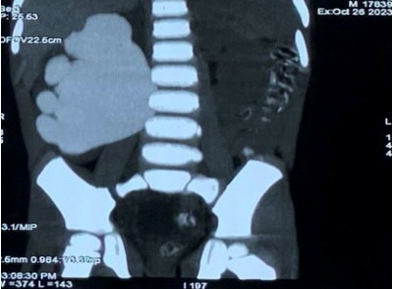

Hình 2. Thận phải giãn lớn trên phim chụp cắt lớp vi tính

Kết quả thăm khám, làm

các xét nghiệm, chụp Cắt lớp vi tính 64 dãy dựng hình 3D hệ tiết niệu, các bác

sĩ chẩn đoán bệnh nhân bị hẹp khúc nối bể thận niệu quản bên phải, nước tiểu

từ thận phải không lưu thông bình thường xuống bàng quang làm cho thận phải bị

giãn dần, bệnh phát hiện ra khá muộn nên thận phải giãn đến độ 4 trong phân độ

4 độ giãn thận trên siêu âm. Bệnh nhân được chỉ định phẫu thuật tạo hình lại khúc

nối bể thận niệu quản bằng phẫu thuật sau phúc mạc đường mổ nhỏ.